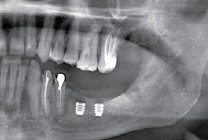

Так вот, чрезмерная атрофия альвеолярного гребня может лишить нас возможности имплантации — нам просто не хватит объемов костной ткани для нормальной установки имплантов. Однако, эта проблема решаема — существует целый ряд методик остеопластики (включая синуслифтинг), позволяющих восстановить любой объем костной ткани в в любом участке зубного ряда с высокой степенью эффективности. И, как правило, хорошие врачи в хороших клиниках так и поступают:

Увы, но подобные методики подходят не всем. Скажем так, я бы десять раз подумал прежде, чем проводить остеопластику пациенту, которому больше 80 лет, у которого есть серьезные проблемы со здоровьем. Также было бы сложно восстановить до необходимого полностью беззубый альвеолярный гребень со значительной атрофией по высоте:

и использовать ультракороткие импланты и другие «оригинальные решения», типа Astratech TX Profile:

Их можно установить в минимально возможный объем костной ткани, где установка обычных взрослых имплантов невозможна без предварительной остеопластики. В некоторых случаях они даже позволяют избежать синуслифтинга, что, согласитесь, звучит очень заманчиво.